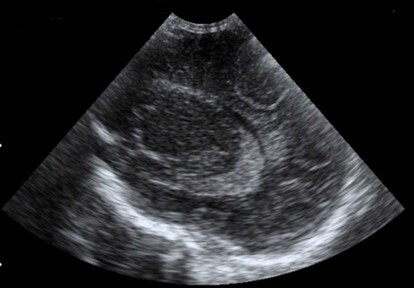

Neonatology Prominent Periventricular Halo Image